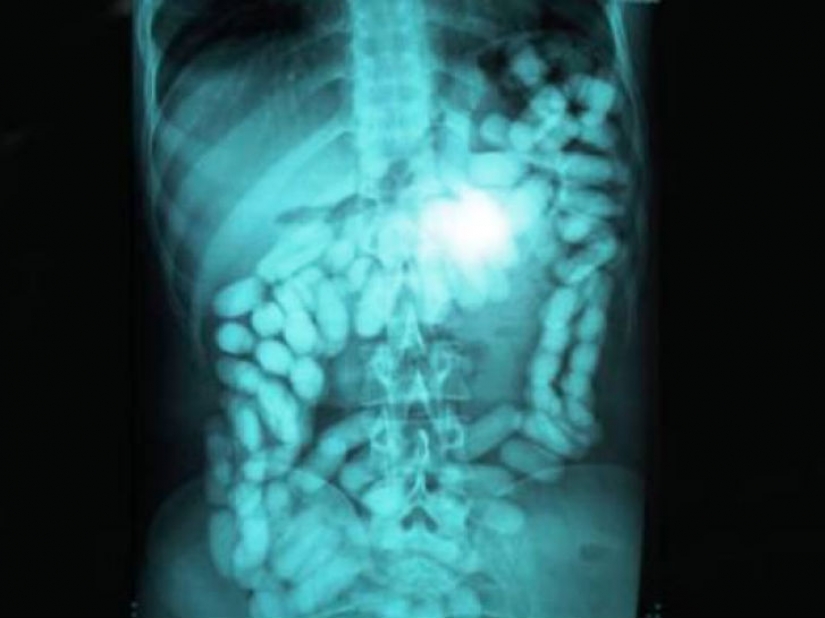

Y es que parece que el hombre que se tragó una gran cantidad de medicamentos para llevar a su contrabando a través de la frontera.